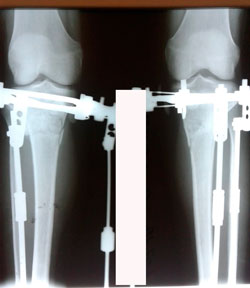

перед крутками

image-31-03-20-05-26-1.jpg